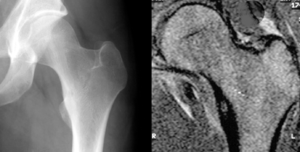

| Osteoid osteoma of the trochanter minor: X-ray and MRI with marked sclerosis around the nidus. | |

Radiographs in osteoid osteoma typically show a round lucency, containing a dense sclerotic central nidus (the characteristic lesion in this kind of tumor), surrounded by sclerotic bone. The nidus is seldom larger than 1.5 cm.

The lesion can in most cases be detected on CT scan, bone scans and angiograms. Plain radiographs are not always diagnostic. MRI adds little to the CT findings which are useful for localisation. Radionuclide scanning shows intense uptake which is useful for localisation at surgery using a hand held detector, and for confirmation that the entire lesion has been removed.[8][9]